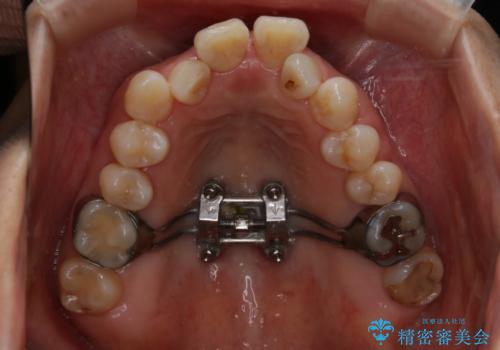

この患者様は骨格的に上あごが小さいことで問題が起きていたため、

上あごを骨ごと広げる必要がありました。

よって治療計画として、インプラントアンカーを使用した上顎急速拡大装置(MARPE)を使用することといたしました。

インプラントアンカーを使用した上顎急速拡大装置(MARPE)について

上あごの裏側(口蓋)に装置をマイクロインプラントで固定し、ネジを回すことで上あごを骨ごと広げていく装置です。

ご自身で回していただくのにコツが必要なのと、広がった直後は前歯に隙間ができてしまうことがあります。

治療中押されるような違和感がありますが、強い痛みはありません。